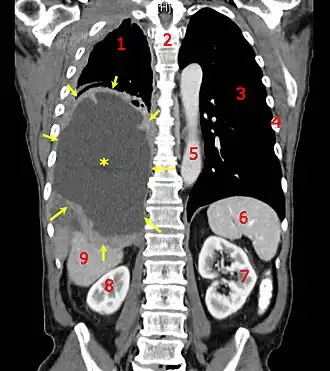

| |

| Tomografia computadorizada mostrando um mesotelioma maligno. 1 & 3, pulmões, 2 espinha dorsal, 4 costelas, 5 aorta, 6 baço, 7 & 8 rins e 9 fígado | |